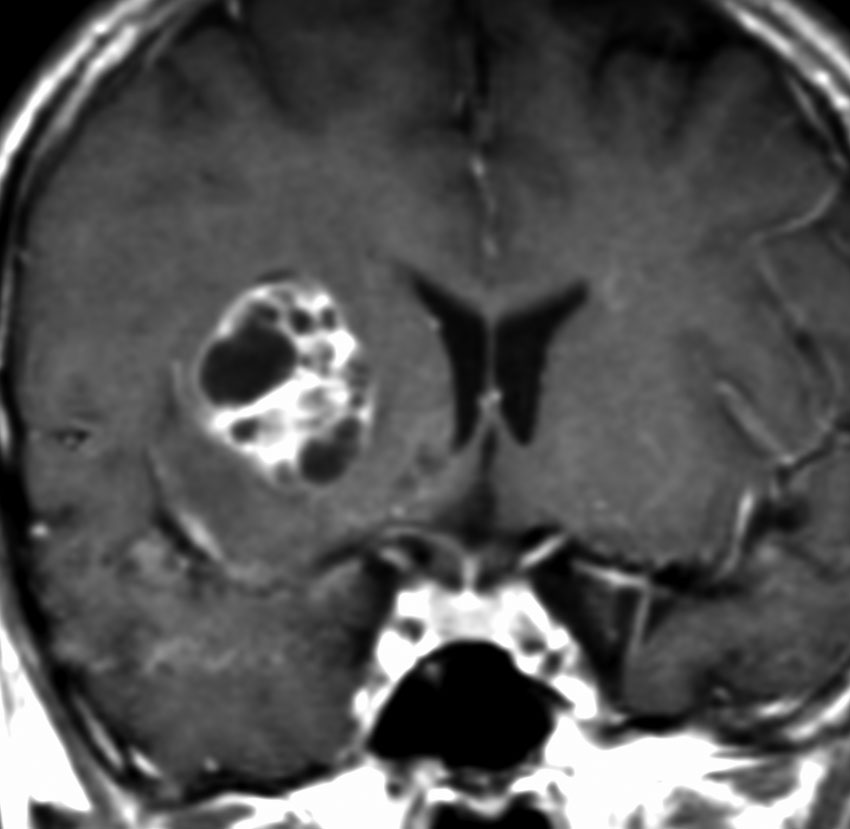

12歳の男児が尿崩症で発症しましたが,7ヶ月間診断がつかずに低ナトリウム血症による全身痙攣を生じました。下垂体と右被殻の2箇所に腫瘍があり,AFP 33ng/ml, HCG-beta 1.0mIUと上昇がみられました。神経下垂体の生検術でgerminomaの診断であったために化学療法が開始されました。CPA, VP-16, CDDP, VCRの併用化学療法に,MTXの髄腔内注入が2回でした。なぜこのような乱暴な化学療法を行なったのかは不明です。当然ですが,下垂体のgerminomaは左側のように消失しました。

でも化学療法中に,右大脳基底核にあった腫瘍が増大して,左のMRIのように脳浮腫も悪化しました。この時点で患者さんが転院してきました。腫瘍マーカーは陰転していて,どう見ても奇形腫が化学療法によるparadoxical responseを生じたものでした。ジャーミノーマが消えて奇形腫だけ増大するという現象です。